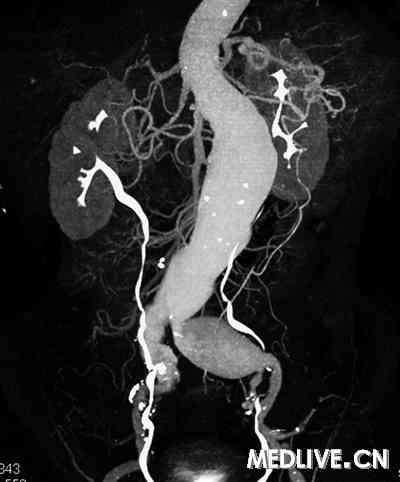

56岁男性患者,因“发现左下腹搏动性包块1个月,反复疼痛1周”入院。既往患者有高血压病3年;入院时血压为180/90 mmHg,左下腹有一个3 cm×3 cm搏动性包块。CT血管造影(CTA)示腹主、左髂总动脉瘤形成,瘤体最大直径分别为4.6 cm和3.7 cm(图1)。患者接受覆膜支架腔内修复术后(图2)痊愈出院。

| 图1 腹主、左髂总动脉瘤形成 |